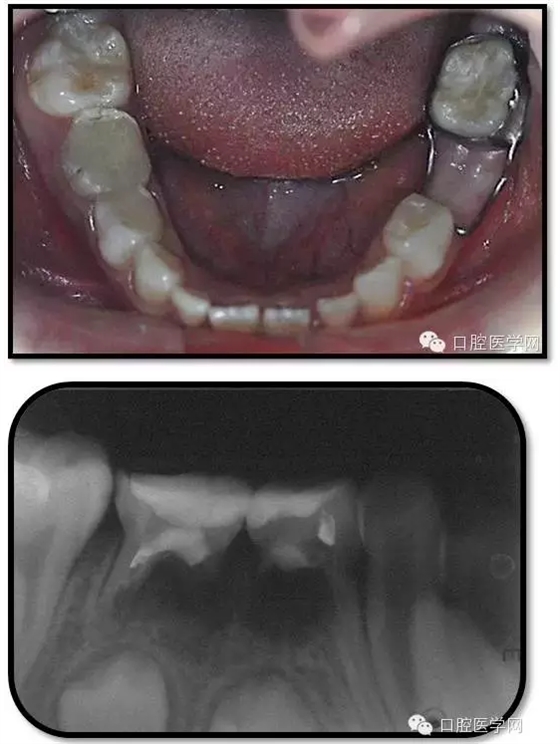

臨床檢查: 75OL齲洞, 舌側(cè)牙體完全劈裂斷端齊齦,探及大量軟化腐質(zhì)。頰側(cè)牙齦紅腫見瘺管,擠壓大量溢膿。叩(±),不松動。X線:75根管空虛,牙根吸收約1/2,根尖周及根分歧大面積透射影,35發(fā)育4期,骨硬板尚連續(xù);51殘根,唇側(cè)牙齦瘺管,叩(±),不松動。X線:51牙根吸收約1/2,根尖周低密度影。

85O、84DO充填體邊緣不密合,叩(±),不松動。84頰側(cè)牙齦略紅腫。X線:84遠(yuǎn)中根及髓室底完全吸收,根分歧透射影,近中根內(nèi)側(cè)見外吸收,44上方骨硬板連續(xù)。85近中根完全吸收,髓室底吸收,根分岐透射影,遠(yuǎn)中根管內(nèi)見根充影像。45發(fā)育4期,骨硬板連續(xù)。

85O、84DO充填完好,邊緣密合,叩(-),不松,齦無紅腫。X線:84、85根分歧透射影,44、45骨硬板連續(xù),恒牙胚上方骨板厚約2-3mm。75帶環(huán)絲圈式間隙保持器完好,無松動,無咬合不適。64MO中齲。 64MO中齲去腐凈,自酸蝕,SEBOND,樹脂充填。 口腔衛(wèi)生宣教,囑3個月后復(fù)診。

1、根分歧處病變姑息保留牙的治療及轉(zhuǎn)歸。 75牙體缺損過大,根分岐大面積透射影并累及根尖周。故拔除后間隙保持。84、85初診時已做過根管治療,有繼發(fā)齲,牙根吸收較多,可見大面積的根分歧病變,但根尖無病變,考慮44、45表面骨硬板連續(xù),故只對患牙進行了繼發(fā)齲充填治療,姑息保留。3個月復(fù)查時,85O、84DO充填完好,邊緣密合,叩(-),不松,齦無紅腫。7個月復(fù)查時85O、84DO充填完好,邊緣密合,叩(-),不松,齦無紅腫。X線:84、85根分歧透射影,44、45骨硬板連續(xù)。 回顧整個治療過程,應(yīng)定期復(fù)查84、85姑息保留牙,且間隔時間不宜過長。觀察根分歧病變的恢復(fù)情況,一旦發(fā)現(xiàn)恒牙胚受累及,則需采取積極措施。